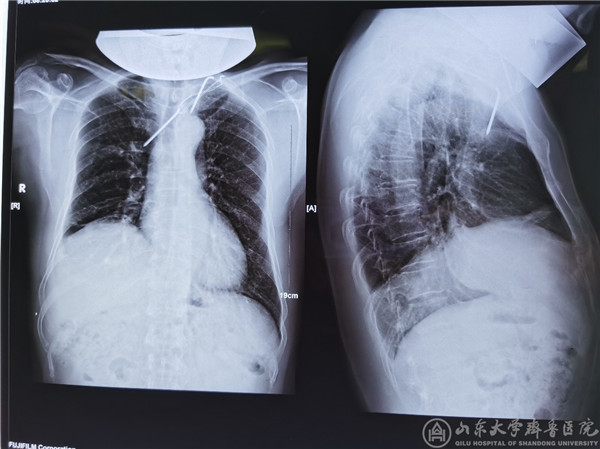

(患者术前X光片)

急诊外科成立12年来,对于创伤急危重症救治、穿刺异物取出等有着非常丰富的经验。桑锡光教授在门诊见到该患者后便意识到病情的复杂性及危险性,立即安排患者入院,随后完善胸部强化CT等检查,进一步明确钢针与周围脏器的关系,游走于患者纵膈内的钢针尖端刺入右肺、主体在上腔静脉和胸廓内动脉之间,横卧在无名静脉之上并对其形成压迫,造成CTA静脉相延迟。钢针尾部有个弯头,贸然拔出极易损伤大血管,导致大出血死亡,后果不堪设想。